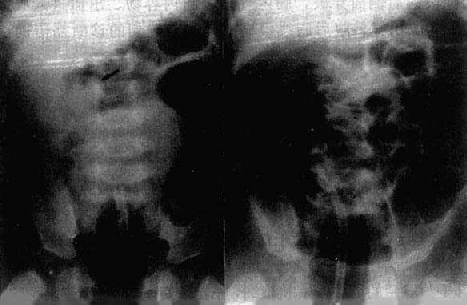

1.单纯性小肠梗阻 梗阻发生后3~6小时可出现X线表现。梗阻近端肠曲胀气扩大。立位像可见肠内高低不等液面,胀气肠曲呈弓形,多发的液面呈梯状排列。早期蠕动亢进,透视可见肠内液面上、下变化活跃。病情发展,肠曲胀气扩大逐渐加重,肠壁张力减低,蠕动明显减弱,液面增宽。肠壁和肠和肠粘膜皱襞除非是慢性梗阻,一般无明显增厚。梗阻远侧肠曲无气或仅见少许气体,因而可根据胀气扩大肠曲所涉及的范围来估计肠梗阻的位置(图4-1-4)。

小肠梗阻(立位)

图4-1-4 小肠梗阻(立位)

中上腹部小肠明显积气、扩张,

有多个液平